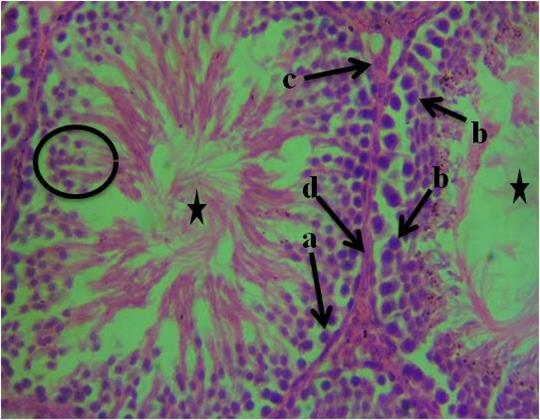

The histological section of group 1 (control) animals given water and feed alone as represented in figure 1 shows normal spermatogonia, primary spermatocytes, interstitial cell of Leydig, connective tissue, spermatids and seminiferous tubules with the presence of densely packed spermatozoa. In figure 2, the histological section revealed proliferation of atypical germ cells within the seminiferous tubules, degenerated connective tissue, necrotic spermatids and few/absence of spermatozoa within the seminiferous tubules. Figure 3 revealed necrotic spermatids, degenerated connective tissue, Leydig cell necrosis, necrosis of spermatogenic cells and deformed seminiferous tubule with very scanty spermatozoa.

Figure I: Photomicrograph of testis of control animals given water and feed alone showing, a- spermatogonia, b-primary spermatocytes, c-interstitial cell of Leydig, d-connective tissue, spermatids (circle) and seminiferous tubules with the presence of densely packed spermatozoa (star). (H&E). 400x magnification.